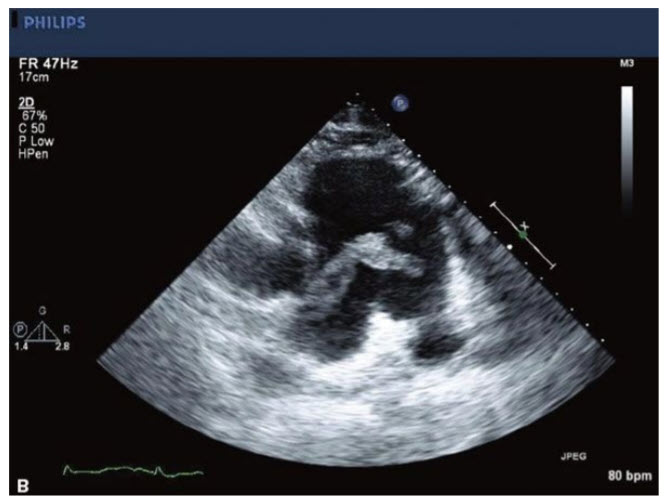

The images in Figures below A and B

are from a transthoracic echocardiogram (TTE) from a patient who is a 57-year-old woman with lung cancer who presents with chest pain (CP) and SOB.

The most likely cause of her CP and SOB based on these images is:

Pulmonary embolus. The images in Figures in question show the parasternal short axis showing specifically the main PA/PA bifurcation. Both images show a large multilobulated echodensity or mass within the main PA which represents a clot in transit. The patient is hypercoagulable due to her malignancy and has developed a deep venous thrombosis which has embolized and is on its way to the lungs. The multilobular appearance shows that this mass is a cast from a deep vein in the leg. The remaining answers are causes of CP; however, these answers do not describe the situation found on TTE. Patients with malignancy can present with tamponade from a pericardial effusion but no effusion is seen on these images.